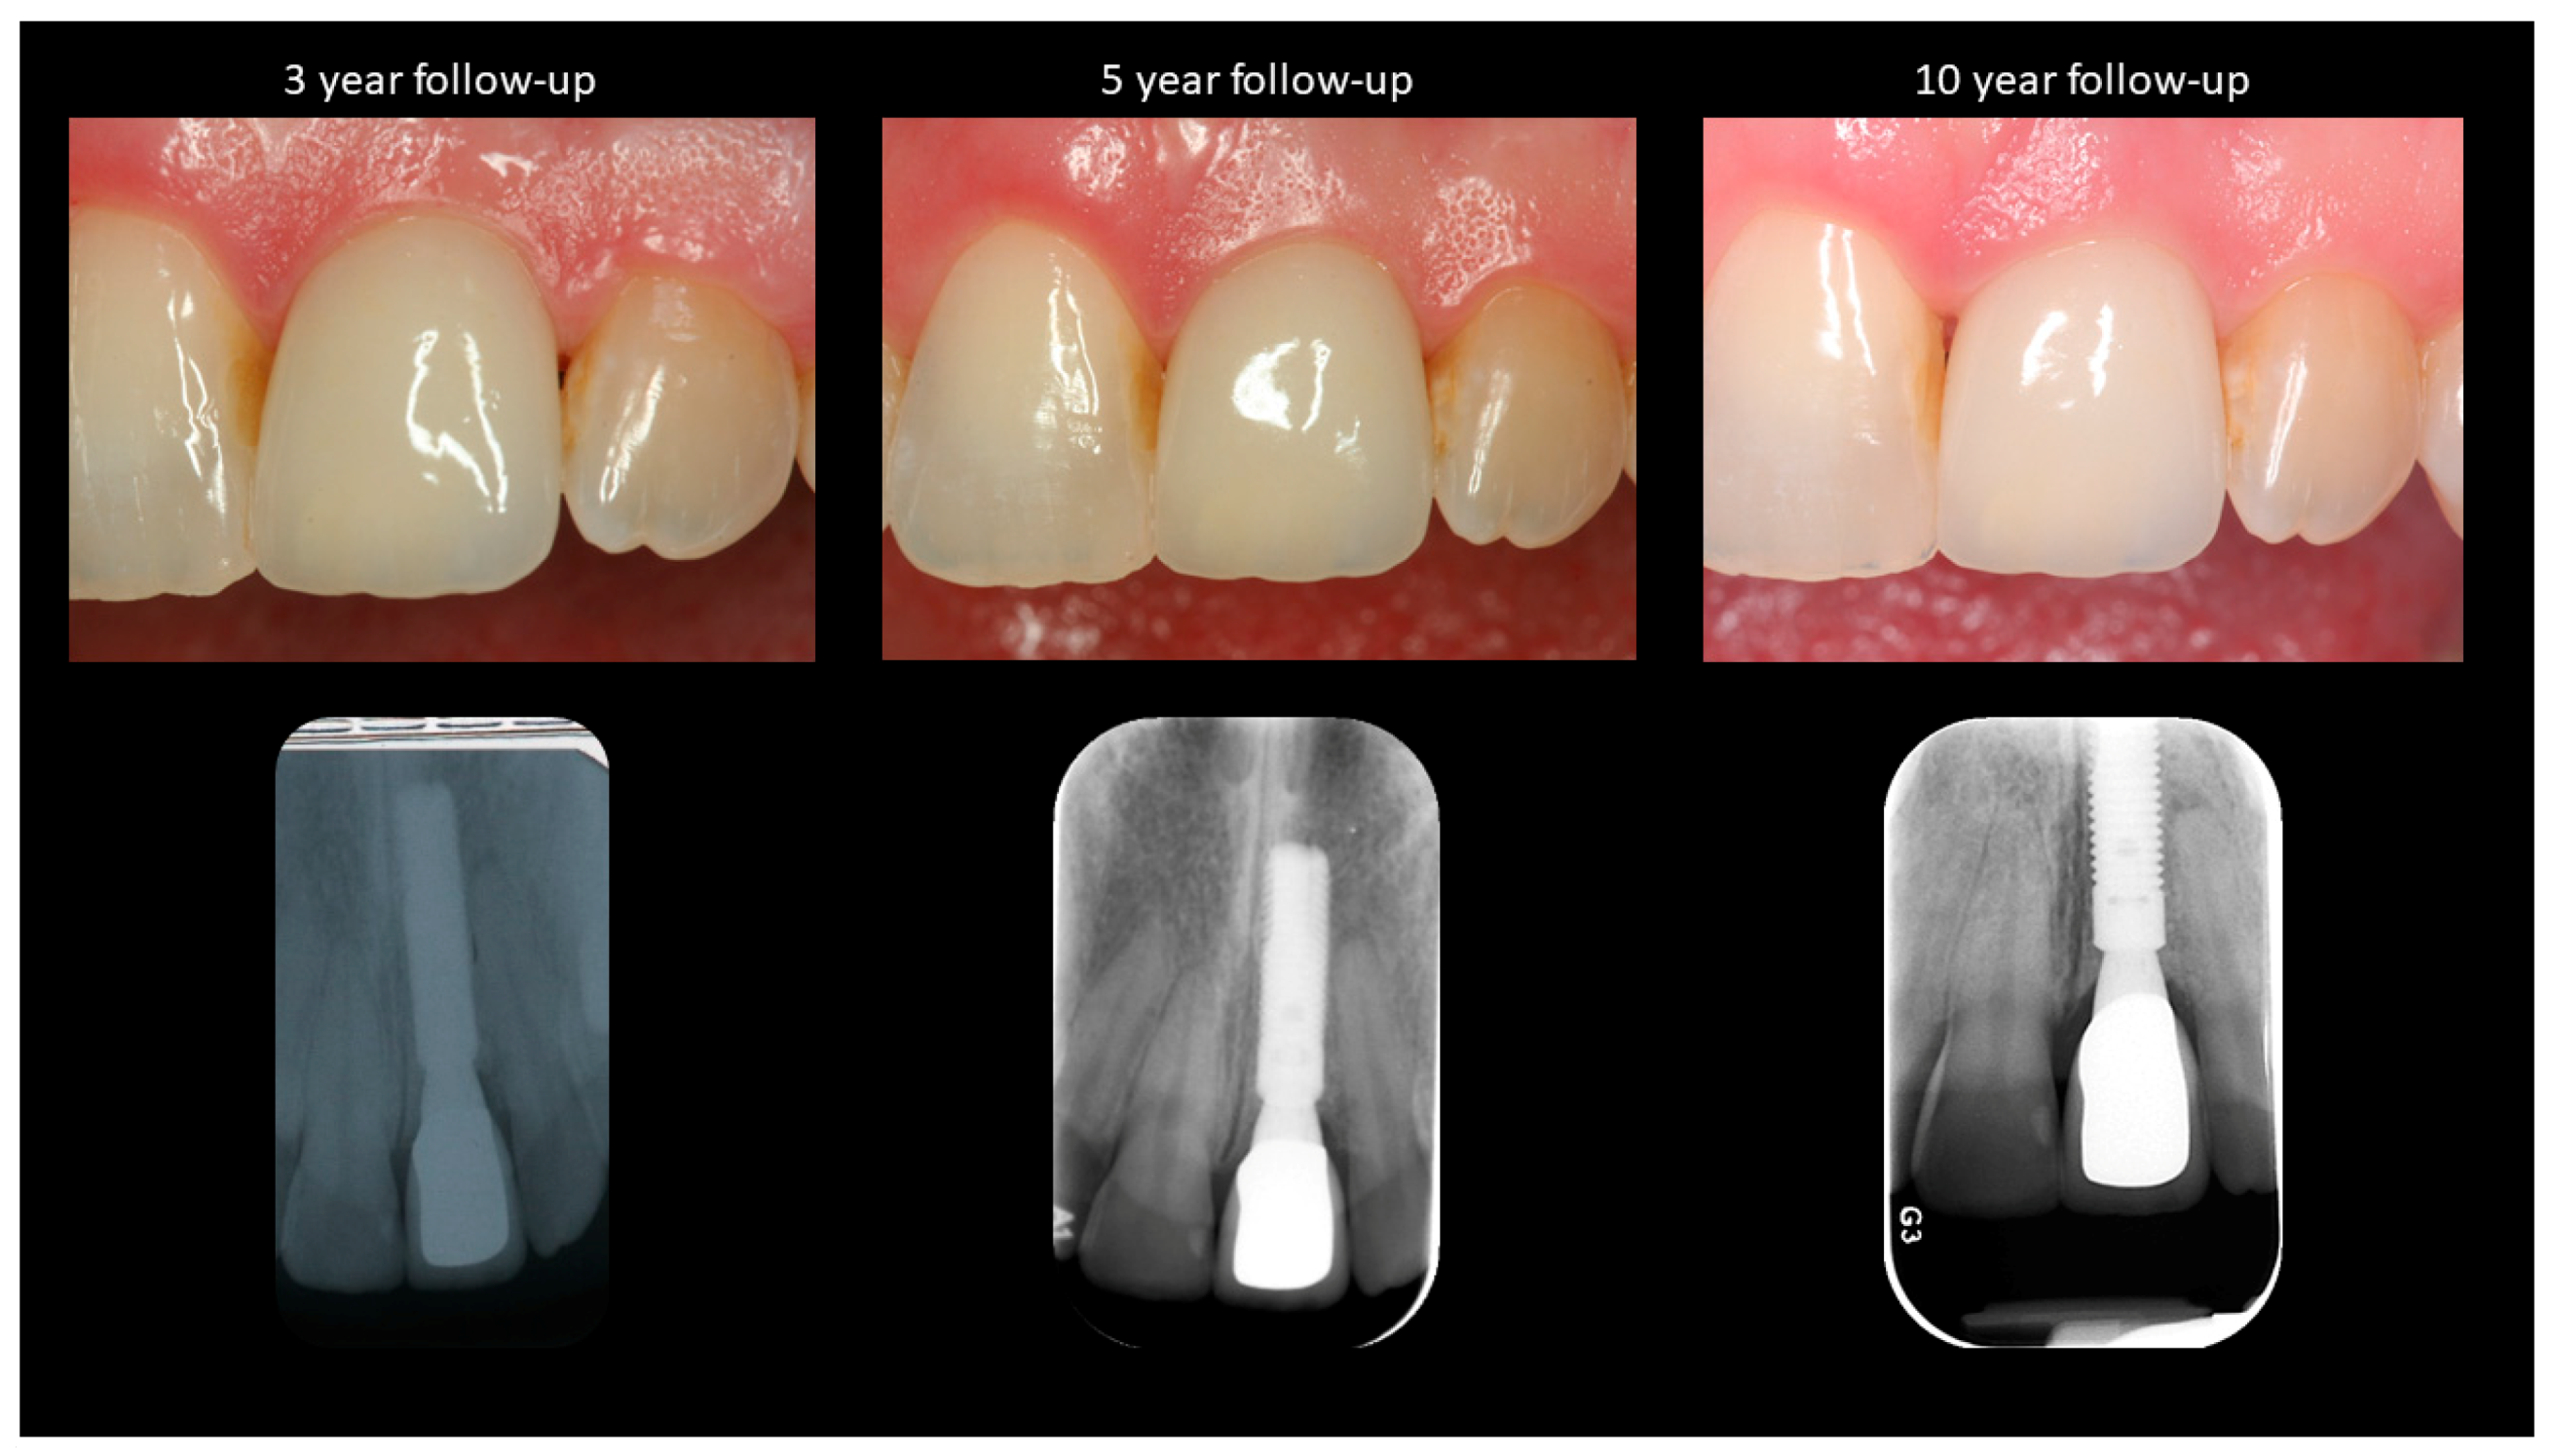

Figure 3.

Peri-implant soft and hard tissue levels at 3, 5, and 10 year follow-up appointments.

Intraoral photographs were taken with the help of a DSLR camera (Cannon 1300D, Cannon Inc., Tokyo, Japan) at a fixed angle and magnification ratio to evaluate the soft tissue changes around the implant (Figure 2 and Figure 3). A periodontal probe with standardized markings was placed on the adjacent tooth to help in image calibration. The images were imported to Image J where the incisal edges of the adjacent teeth were used to draw a reference line based on which the changes in the papillae and midfacial soft tissue levels were calculated, as described previously [5].

Figure 2 and Figure 3 show the clinical photographs and radiographs from baseline (T0) to the final follow-up (T5). A minor gain in the midfacial mucosal margin was observed between implant placement and connection of the definitive crown (Table 1). The midfacial mucosa remained stable after the insertion of the crown to the 10-year follow-up. Mesial and distal papilla levels remained stable between the T0–T4 time points. Although no changes were seen in the distal papilla, a slight change was observed in the mesial papillary level between T4–T5 (Table 1). A slight improvement was observed in the aesthetic outcomes as measured with the help of PES. The overall PES improved from 10 at T0 to 11 at T5.

Evaluation of the bone levels around the implant revealed an overall gain of 0.7 mm on the mesial and distal aspects between implant placement and 10-year follow-up (Table 1).

Levels of midfacial mucosal margin remained stable throughout the 10-year period. Soft tissue recession has been considered to be unpredictable around immediate implants according to a few studies [10,11,12], whereas other studies have reported stable mucosal margins after immediate placement [5,13,14]. When considering the papillae, the distal papilla levels remained stable whereas a recession of 1 mm was observed at the mesial papilla. Most of this recession was observed after five years in function. This may have been the result of changes in the level of interproximal bone on the adjacent central incisor.